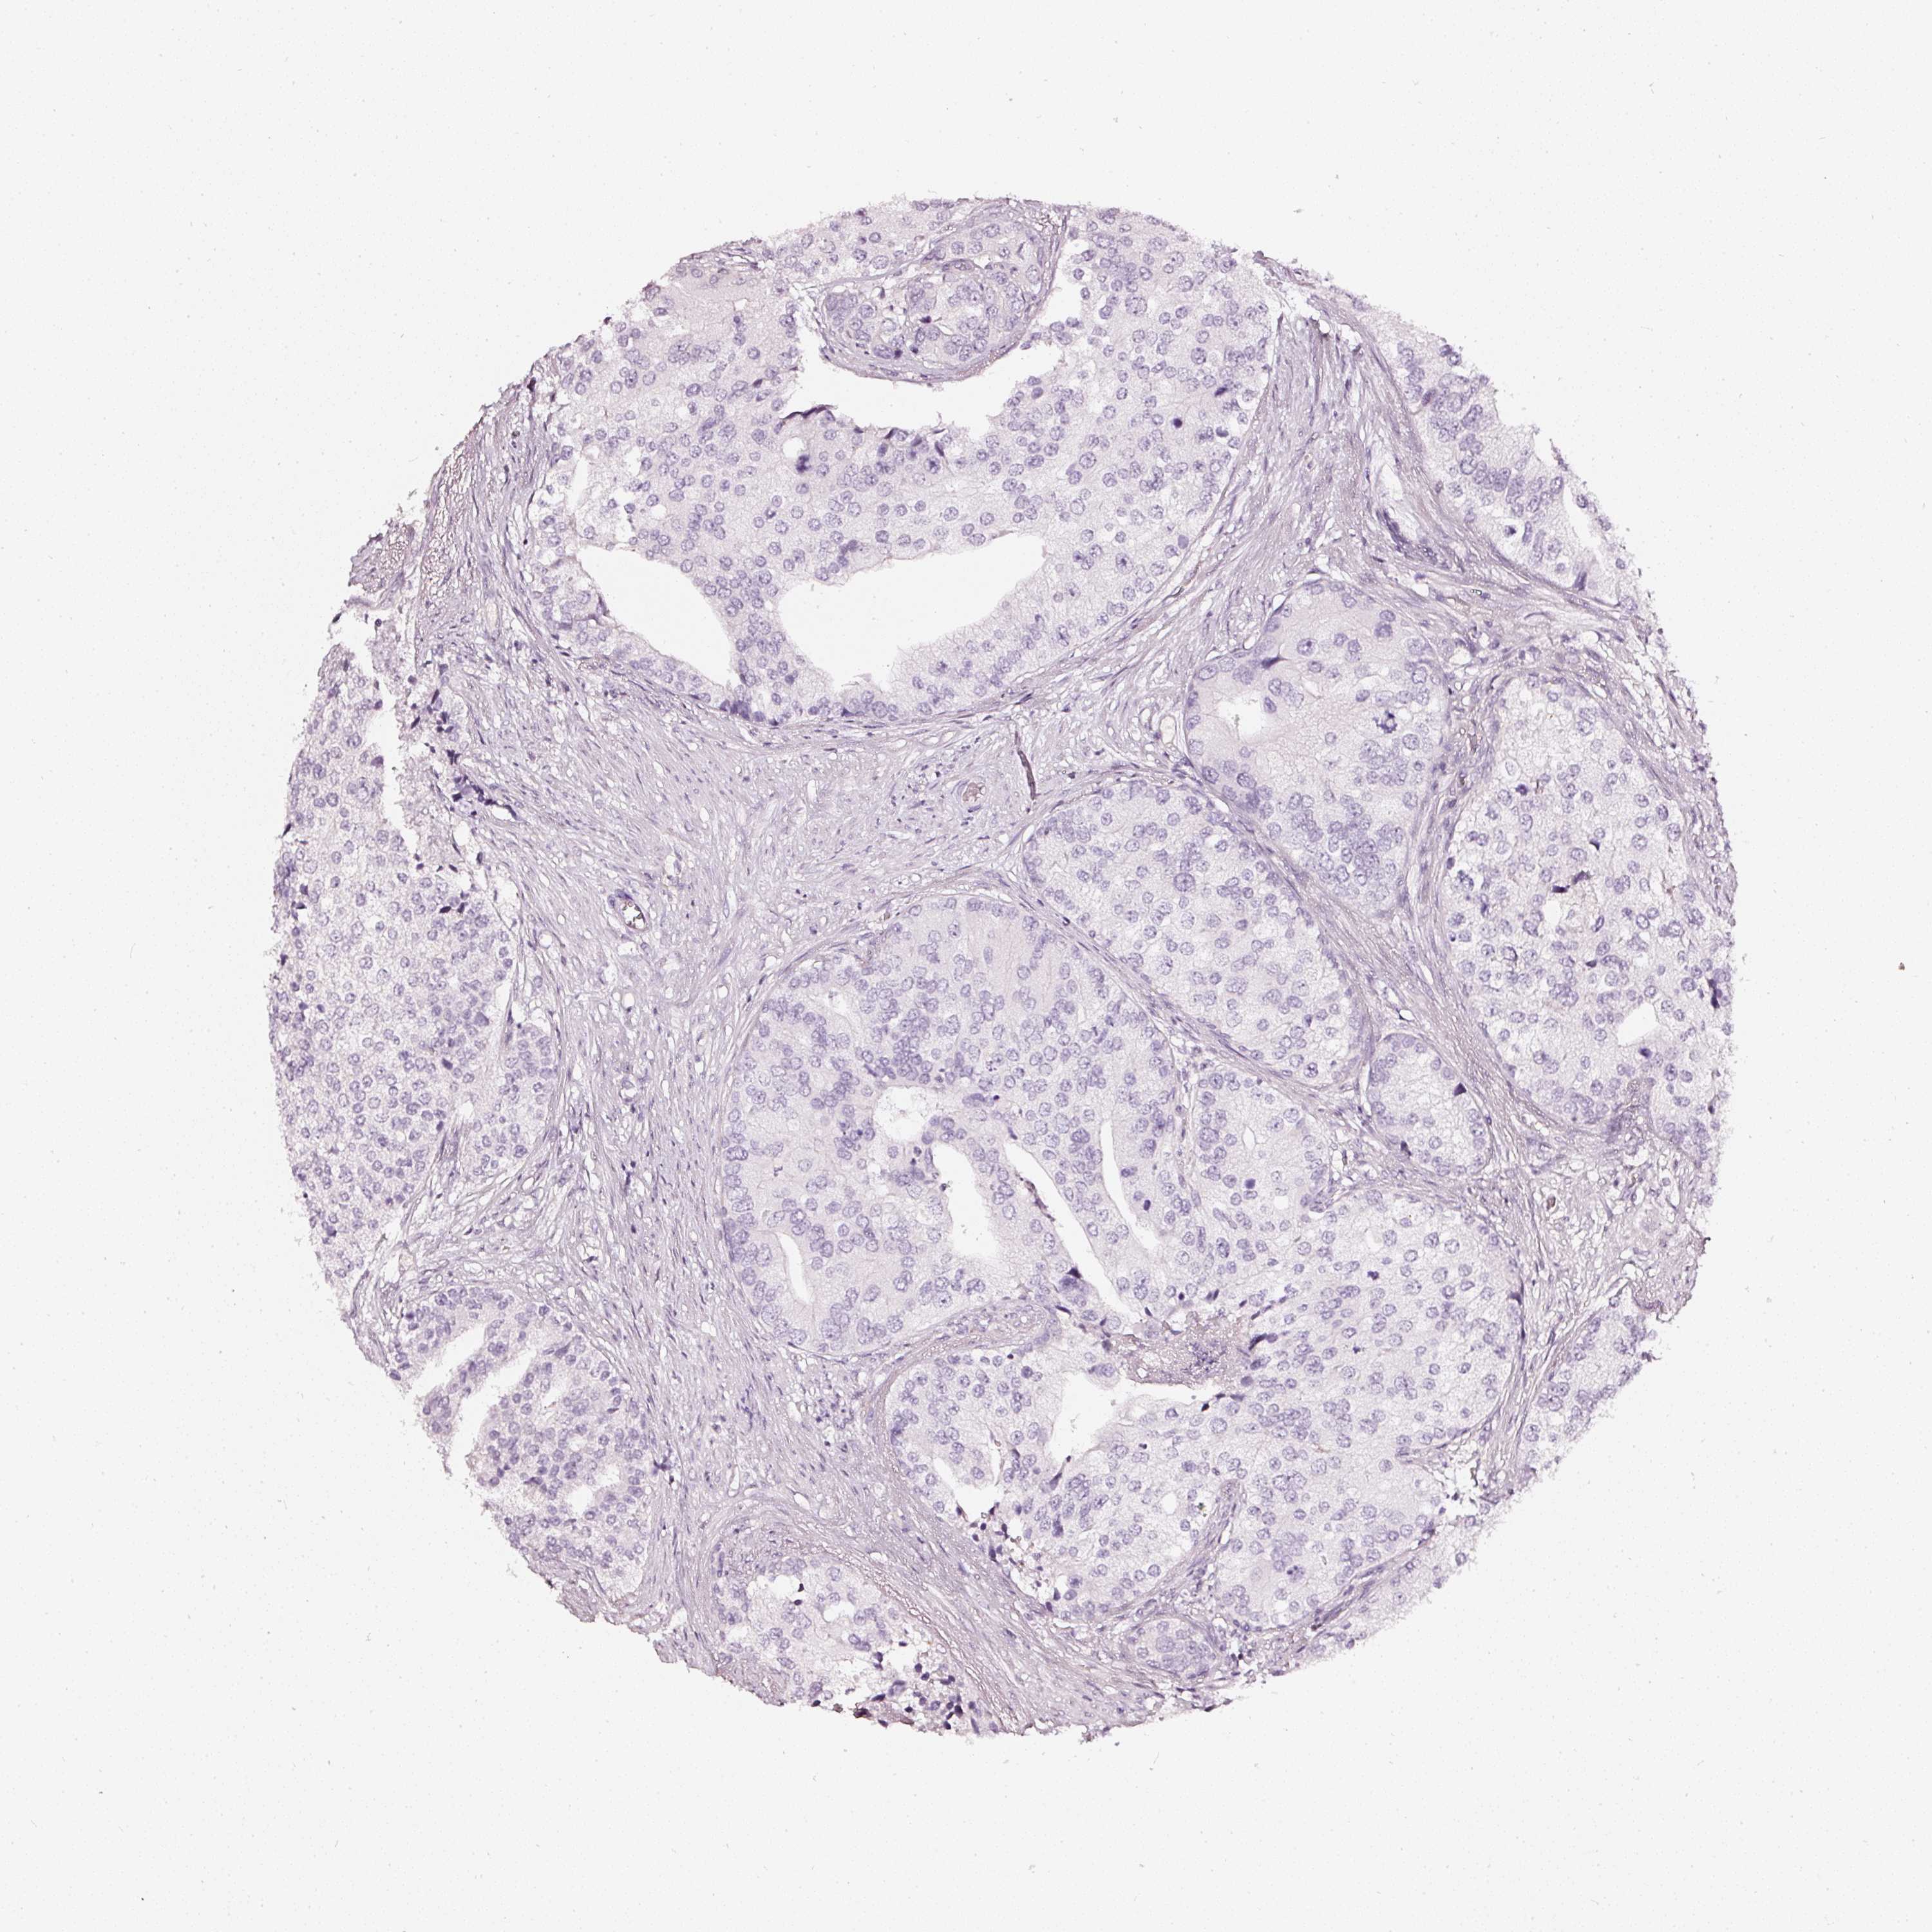

PROSTATE CANCER - Protein expressioni

A mouse-over function shows sample information and annotation data. Click on an image to view it in a full screen mode. Samples can be filtered based on level of antibody staining by selecting one or several of the following categories: high, medium, low and not detected. The assay and annotation is described here.

Antibody stainingi

Antibody staining in the annotated cell types in the current human tissue is reported as not detected, low, medium, or high, based on conventional immunohistochemistry profiling in selected tissues. This score is based on the combination of the staining intensity and fraction of stained cells.

Each image is clickable and will lead to virtual microscopy that enables deeper exploration of all samples and also displays staining intensity scores, fraction scores and subcellular localization as well as patient and tissue information for each sample.

HPA023266

HPA023278

HPA023280

HPA023338

CAB002672

Staining

High

Medium

Low

Not detected

Intensity

Strong

Moderate

Weak

Negative

Quantity

>75%

75%-25%

<25%

None

Location

Nuclear

Cytoplasmic/membranous

Cytoplasmic/membranous,nuclear

Adenocarcinoma, High grade

Adenocarcinoma, Low grade

Adenocarcinoma, NOS

Adenocarcinoma, Medium grade